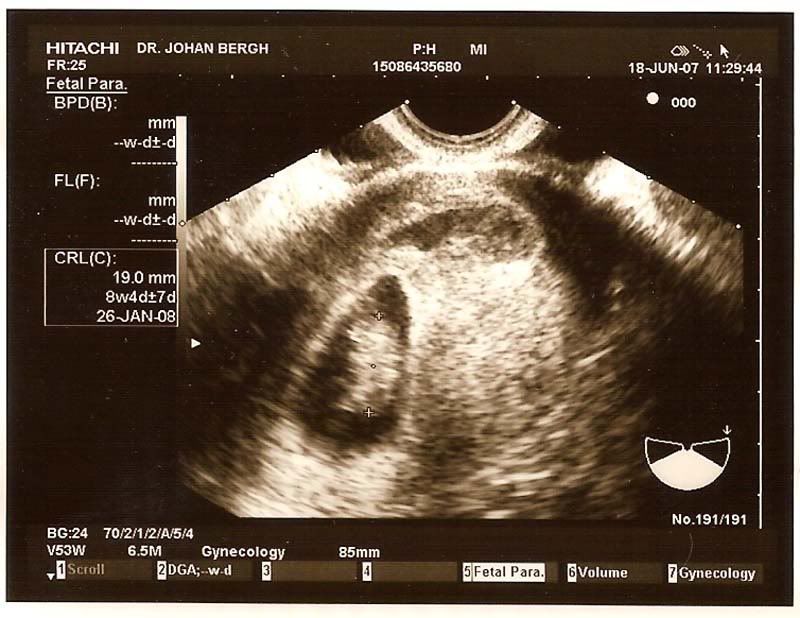

baby2010? Skrevet 18. juni 2007 Forfatter #13 Skrevet 18. juni 2007 Jeg var litt mindre på vei enn jeg trodde, var 8+4. Var ikke kjempe masse å se, men en liten klump Fikk også se hjerte slå og høre hjertelyden. Var veldig kjekt! Her er ultralydbildet: http://i91.photobucket.com/albums/k316/Audhild_2006/Ultralyd18_6_07red2.jpg Jeg blødde veldig mye i begynnelsen. Masse rødt blod og ganske store klumper. Nå den siste tiden har det for det meste vært brunt. Legen sa til meg at det ikke var noe farlig for barnet at jeg blør, for blødningen er oppfor/nedfor barnet. Mest sannsynlig er det en blodkar som har "sprukket". Hvis du ser på ul bildet vil du se blødningen....det er den ovale flekken som er ett stykke oppfor fosteret. Blødningen ligger vannrett.